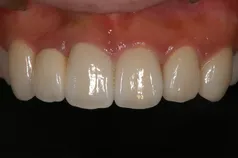

[症例]

矯正治療を行っています。

治療前は上下の歯が反対になっている所もあり、上の歯の真ん中から2本目の歯は矮小歯と言って、平均より小さな歯のため上唇が引っ込んで見えます。

インビザラインでマウスピース矯正後、オフィスホワイトニングを行い、矮小歯はラミネートベニアで修復しました。

綺麗な歯並びになるとともに、上顎の歯列のアーチが広がって、上唇がやや前方に出ることで自然な口元になりました。

- 治療期間: 1年6ヶ月

- 治療回数: 10回

- 費用: 120万円

- デメリット:治療後に矯正の後戻り防止のためのマウスピースを使用しなければならない